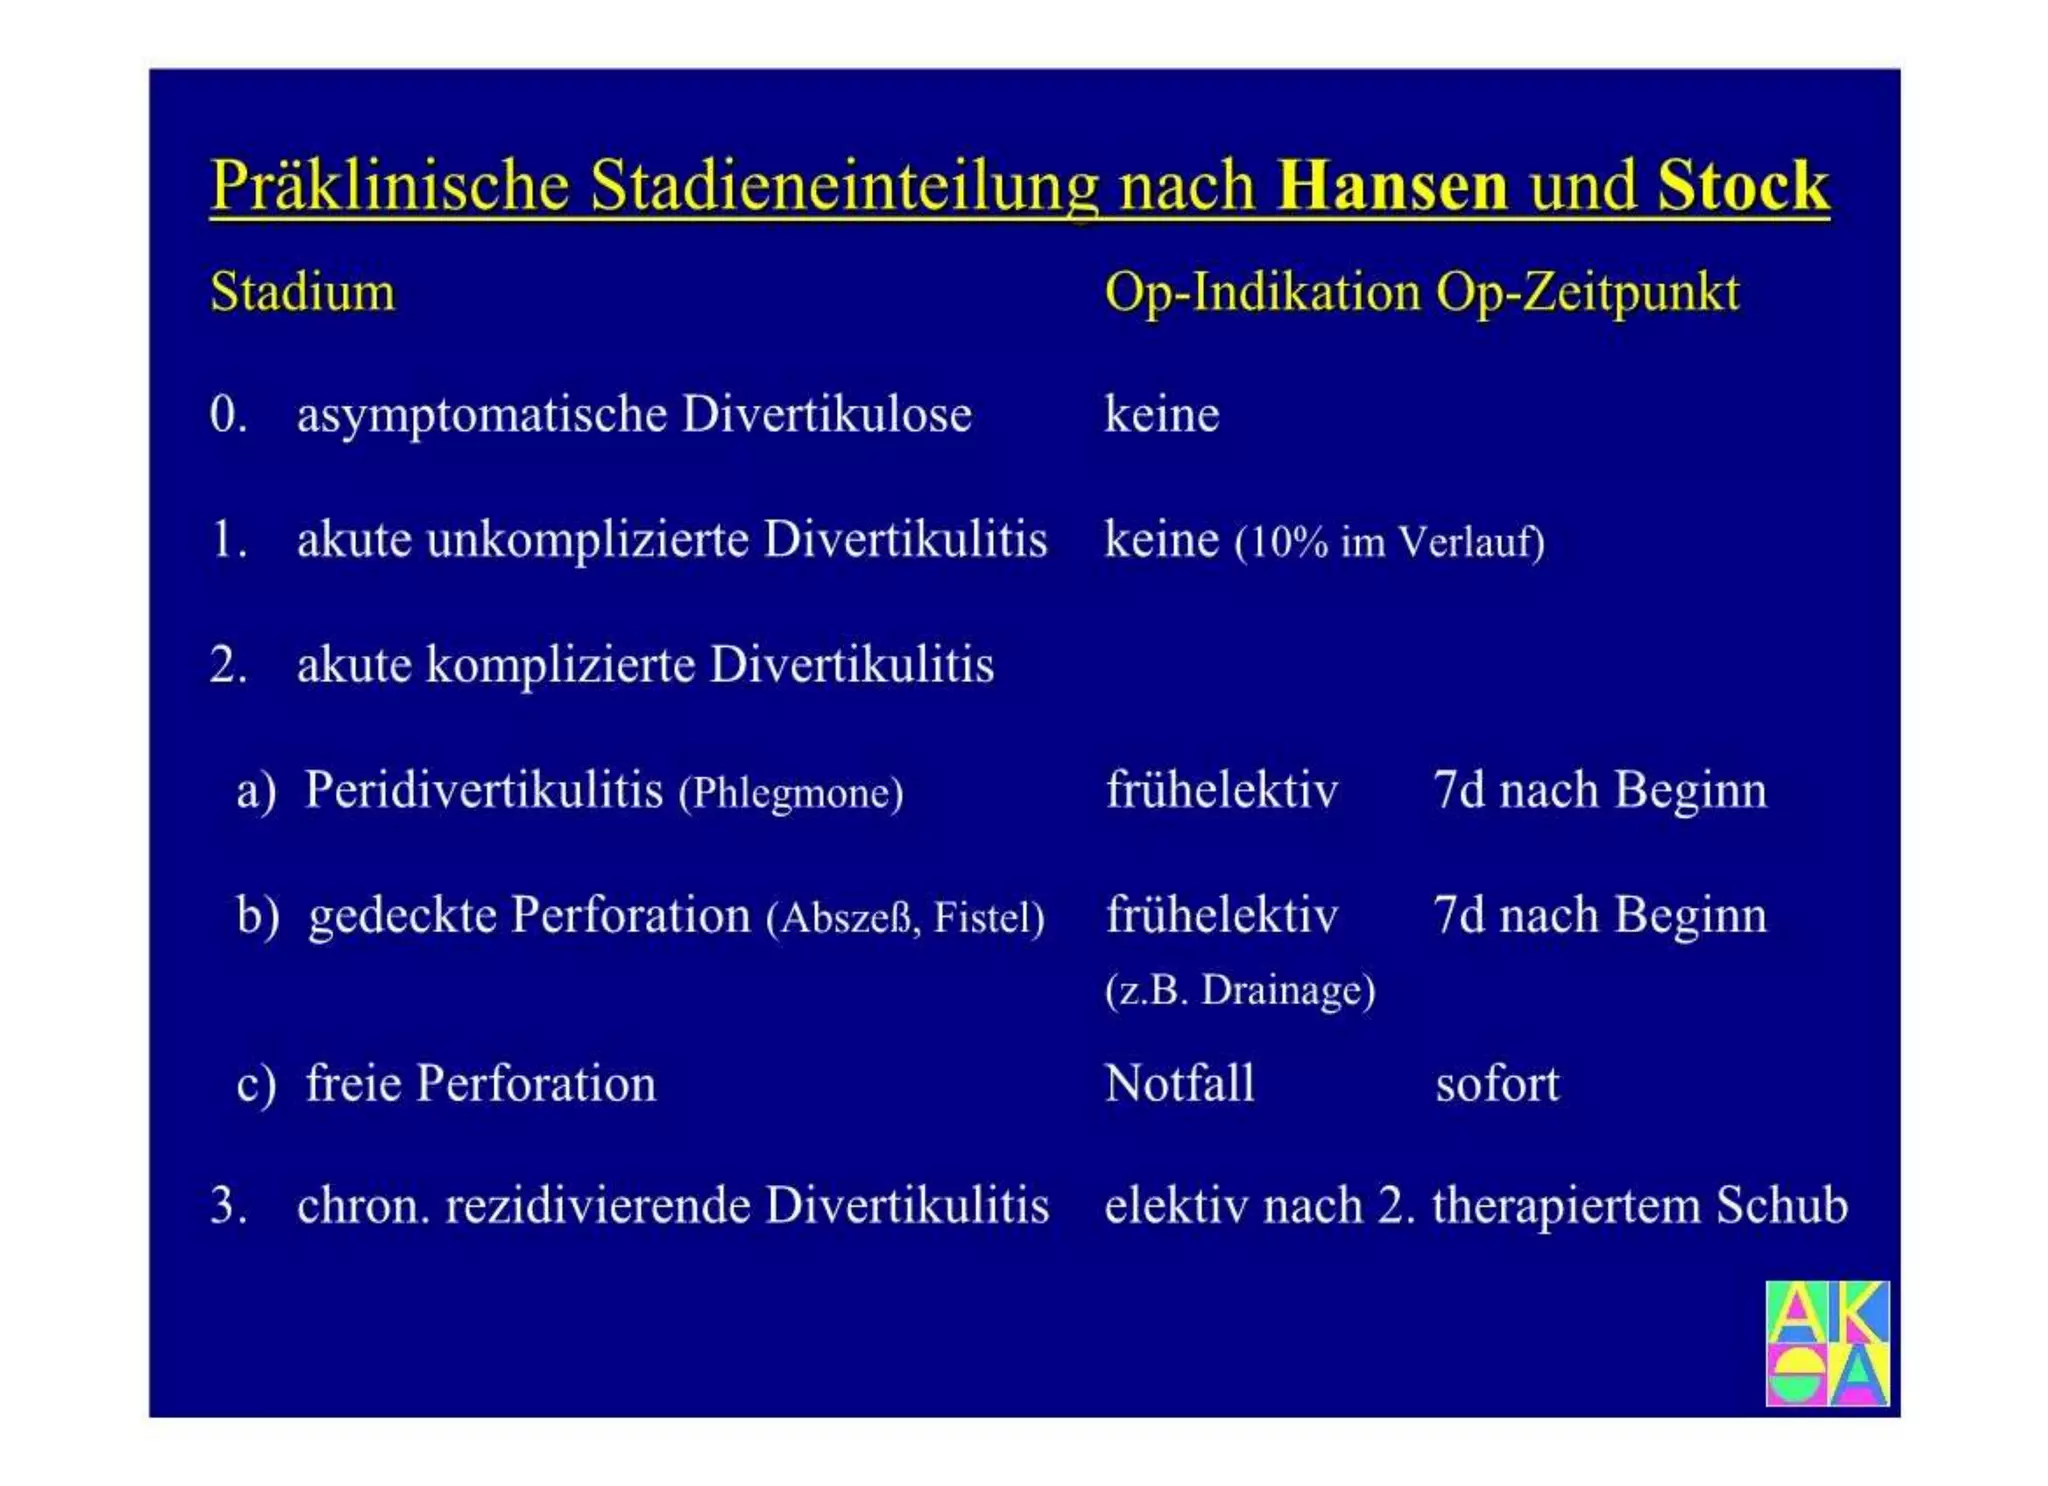

Chronische Enteropathie und Ileus, Dünndarm und Dickdarmdiagnostik, Mechanischer und paralytischer Ileus, Eingeklemmte Darmabschnitte, aufgereihter Bridenileus, und dazu Dickdarmileus, eingeklemmte Hernien, Weitergabeskript